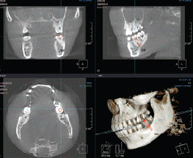

3차원 정밀진단 시스템

얼굴 골격을 빠짐없이 분석합니다

얼굴 골격의 모든 방향을 빠짐없이 촬영하고

치아와 치조골의 상태 및 잇몸뼈의 양과 길이 등의

전반적인 상태를 정확하게 측정하고 진단하여

한치의 오차 없는 시술로 진료의 안정성을 높힙니다.